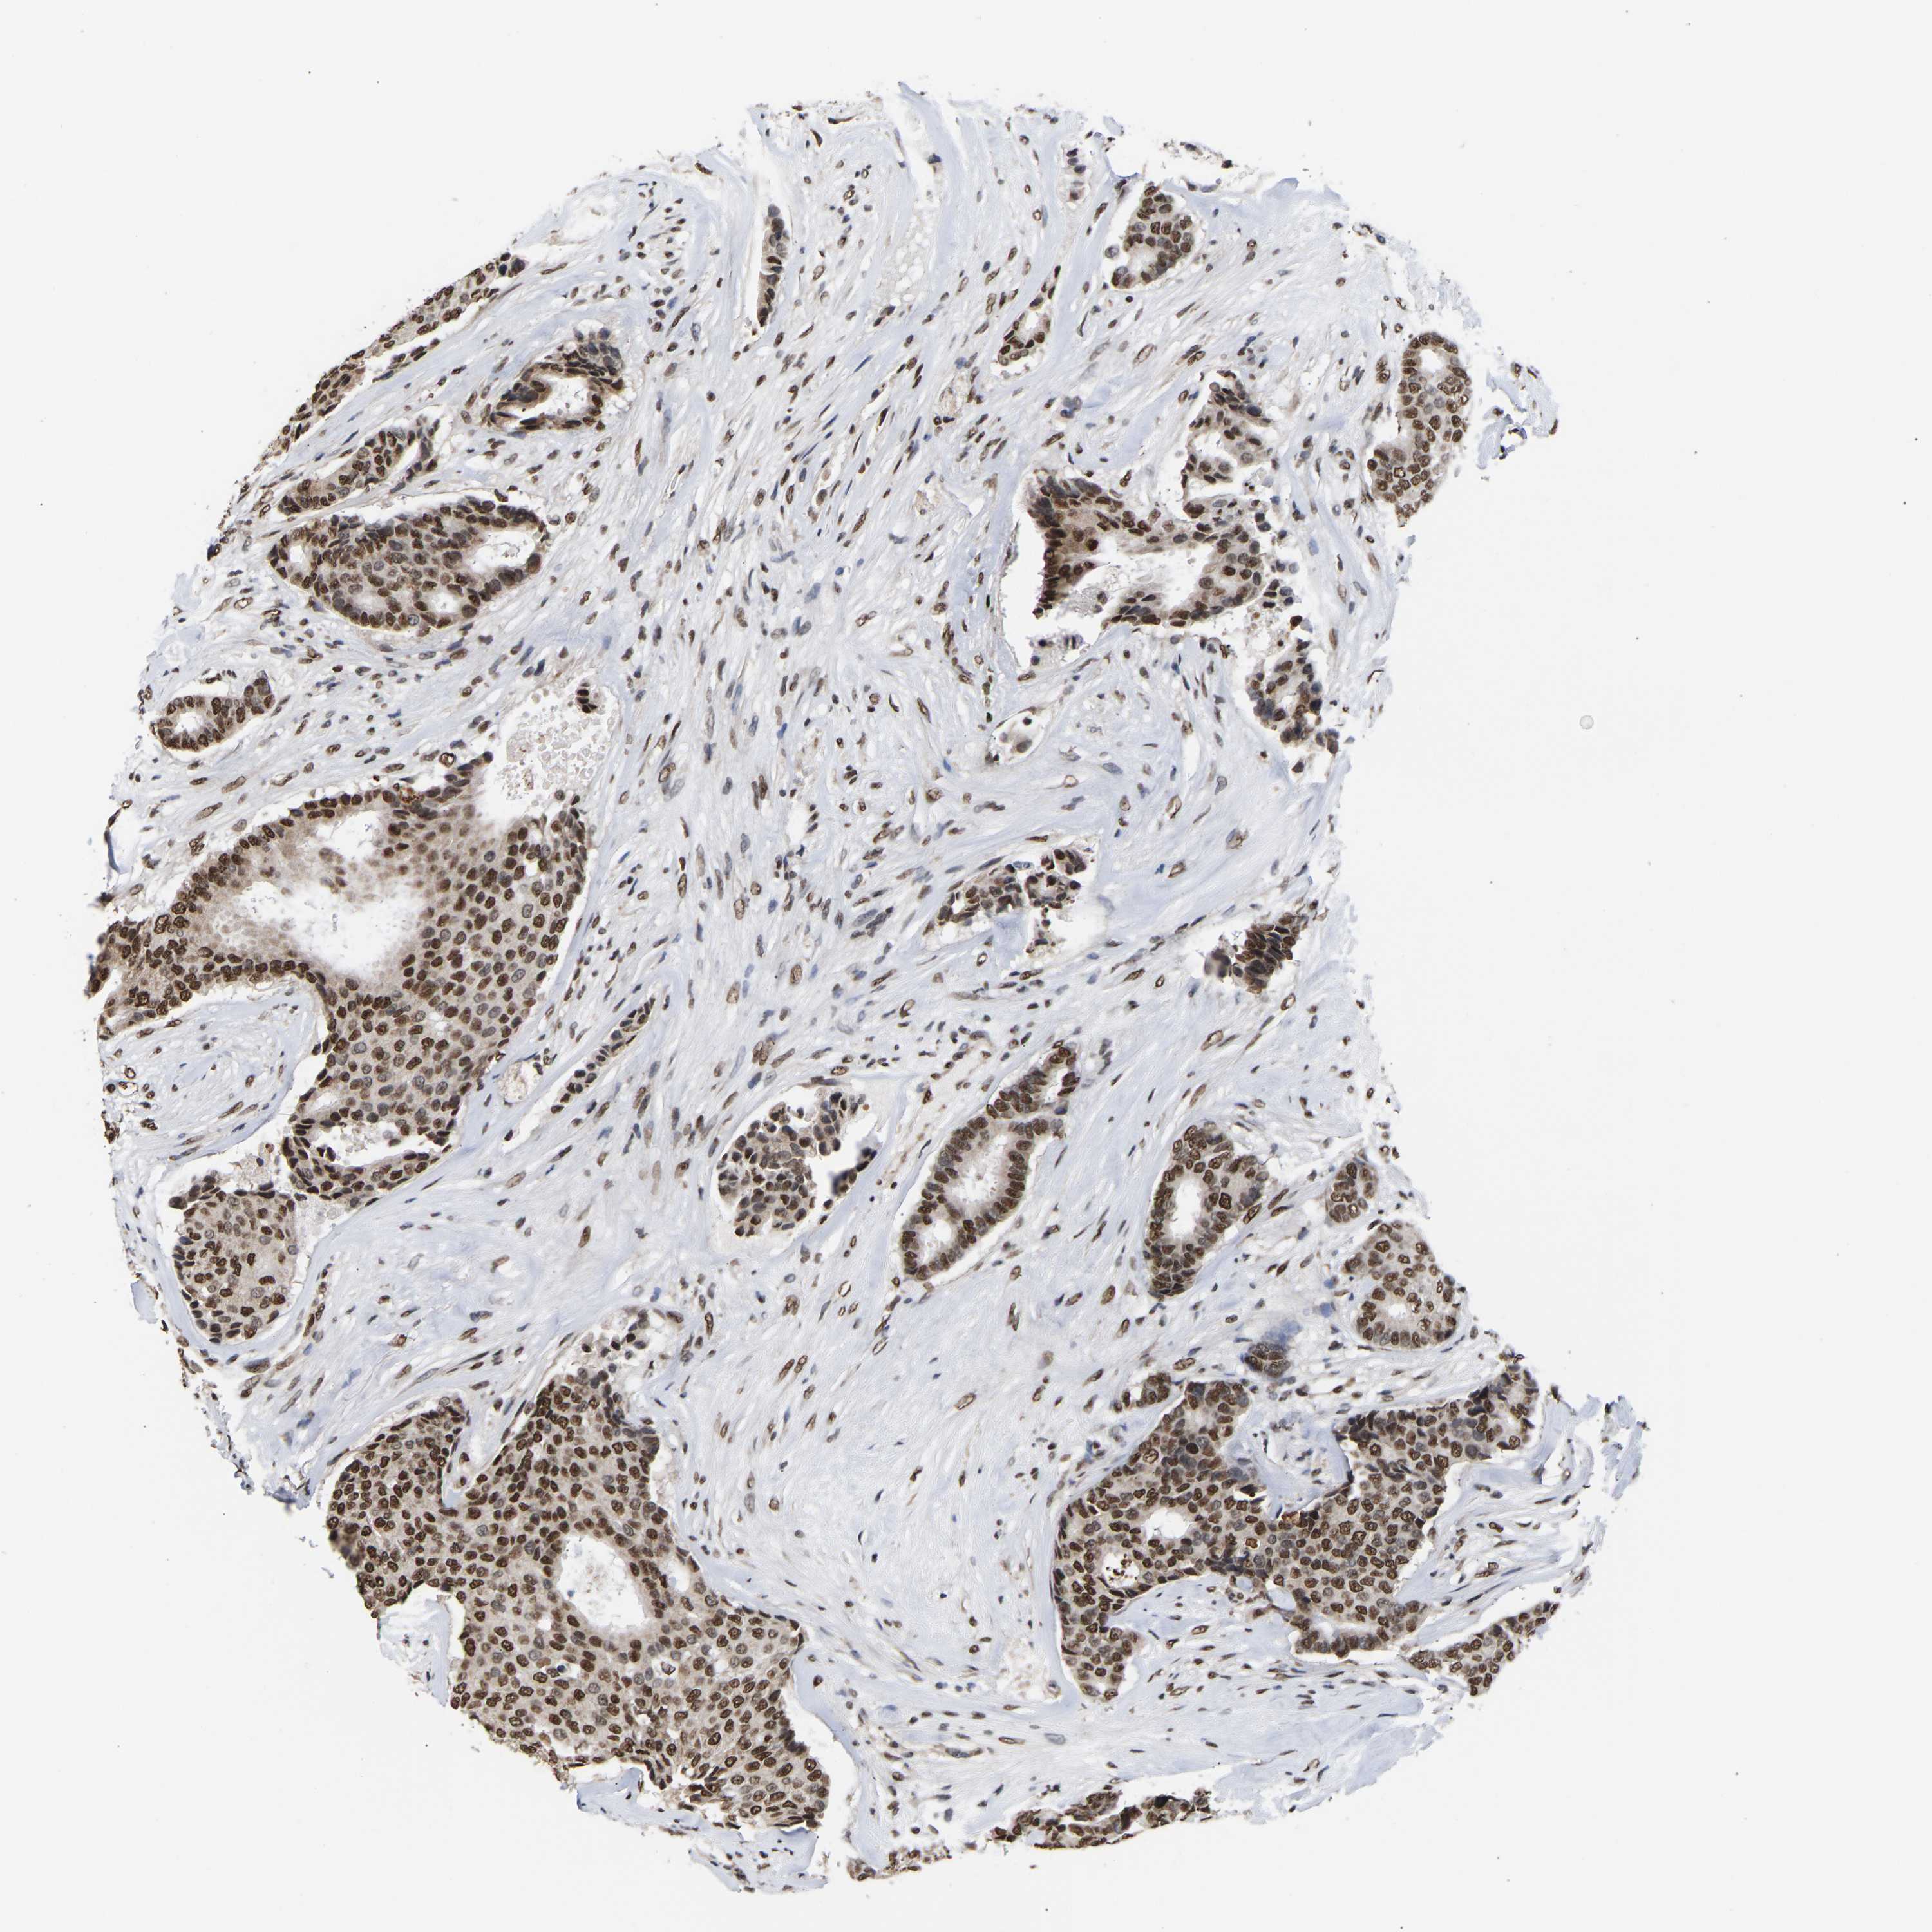

CANCER BREAST CANCER Show tissue menu

BRCA TCGA BRCA VALIDATION PROTEIN EXPRESSION